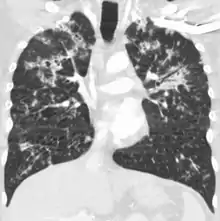

Miliary tuberculosis is a form of tuberculosis that is characterized by a wide dissemination into the human body and by the tiny size of the lesions (1–5 mm). Its name comes from a distinctive pattern seen on a chest radiograph of many tiny spots distributed throughout the lung fields with the appearance similar to millet seeds—thus the term "miliary" tuberculosis. Miliary TB may infect any number of organs, including the lungs, liver, and spleen.[2] Miliary tuberculosis is present in about 2% of all reported cases of tuberculosis and accounts for up to 20% of all extra-pulmonary tuberculosis cases.[3]

X-ray, 13 days after onset, showing bilateral interstitial infiltrates